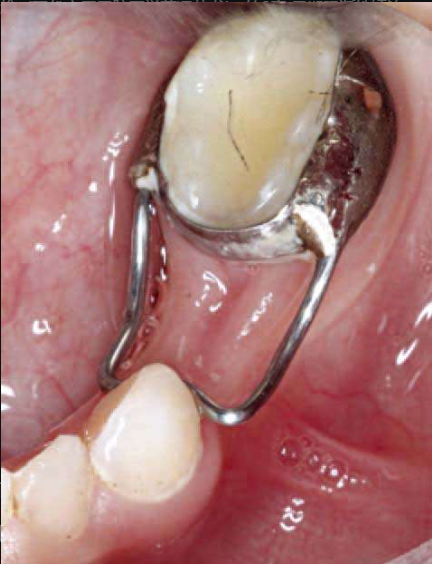

图7 埋伏尖牙使用Ballista弹簧牵引

图8 埋伏尖牙使用Ballista弹簧牵引

(2)能从口内摸到的埋伏牙好做,摸不到的可能牵不出来。在颊侧能摸到的埋伏牙一般都能牵出来,腭侧的埋伏牙不能摸到则不好牵引。

埋伏牙根尖距离原始正确位置越近越好做,根尖距离正常位置越远越不好牵引。如果埋伏尖牙长轴与矢状面交角超过55°,基本上无法牵引出来。